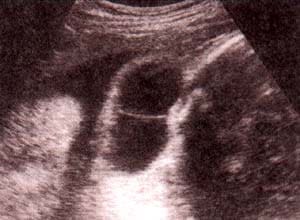

fig. 60. – (a). excencefalia. 18 semanas. se observa tejido cerebral flotando libremente en ausencia de calota. asociado un defecto lumbosacro. |

fig. 60. – (b). 25 semanas. corte frontal. es clara la ausencia de calota con tejido cerebral expuesto. |